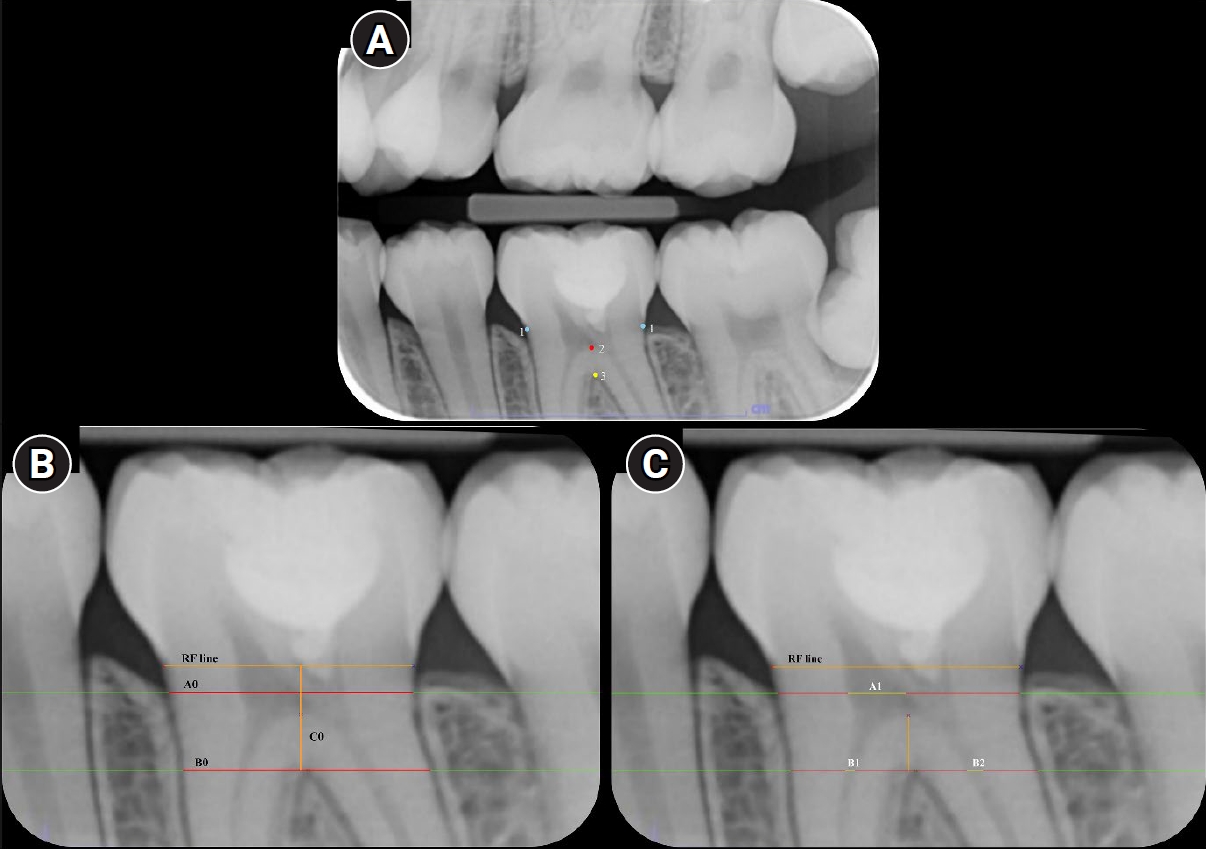

Bitewing radiographs were excluded if the necessary reference points in Figure 1A, including the cementoenamel junction points on the distal and mesial external tooth surfaces, the highest point of the pulp chamber floor, and the highest point of the furcation of the tooth, were not identifiable by the primary investigator (AB).

Reference points and lines on a bitewing radiograph used in this study. (A) Reference points: (1) blue points were the cementoenamel junction points on the distal and mesial external tooth surfaces; (2) a red point was the highest point of the pulp chamber floor; and (3) a yellow point was the highest point of the furcation. (B) Reference lines (RF line): the line connecting the mesial and distal cementoenamel junction points; B0 is a horizontal line/distance, paralleling to the RF line, between the mesial and the distal external root surfaces at the level of the fornix of furcation; C0 is the vertical and perpendicular line/distance between the RF line and the B0 line; A0 is the horizontal line/distance, paralleling to the RF line, between the mesial and the distal external root surfaces at the level of the occlusal one fourth of the C0 distance. (C) RF lines: A1 is the horizontal distance of pulp chamber from the mesial to the distal external pulp chamber surfaces at the level of the occlusal one fourth of the C0 distance; B1 is the horizontal distance of the mesial canal at the level of the fornix of furcation; B2 is the horizontal distance of the distal canal at the level of the fornix of furcation and C1 is the vertical distance between the floor of pulp chamber point and the fornix of furcation point.

To avoid discrepancies in radiographic image expansion or distortion, the semi-automated CMU–PSM program was specifically developed to linearly measure the pulp space using four pulp/tooth proportion values on bitewing radiographs. When using the CMU–PSM program, the evaluators manually selected the reference points in Figure 1A; the program then automatically created the reference lines in Figure 1B and C. The evaluator checked and manually adjusted the margin of the reference lines as appropriate. Finally, the CMU–PSM program automatically calculated four pulp/tooth proportion values, including pulp chamber width (A1/A0), pulp canal widths (mesial, B1/B0, and distal, B2/B0), and pulpal floor thickness (C1/C0). However, the A1/A0 value was not available for teeth treated with CP because their pulp chamber was completely occupied with pulp-dressing material. All pulp/tooth proportion values were exported to a Microsoft Excel table, and the change (∆) in these values from the baselines was computed as follows: